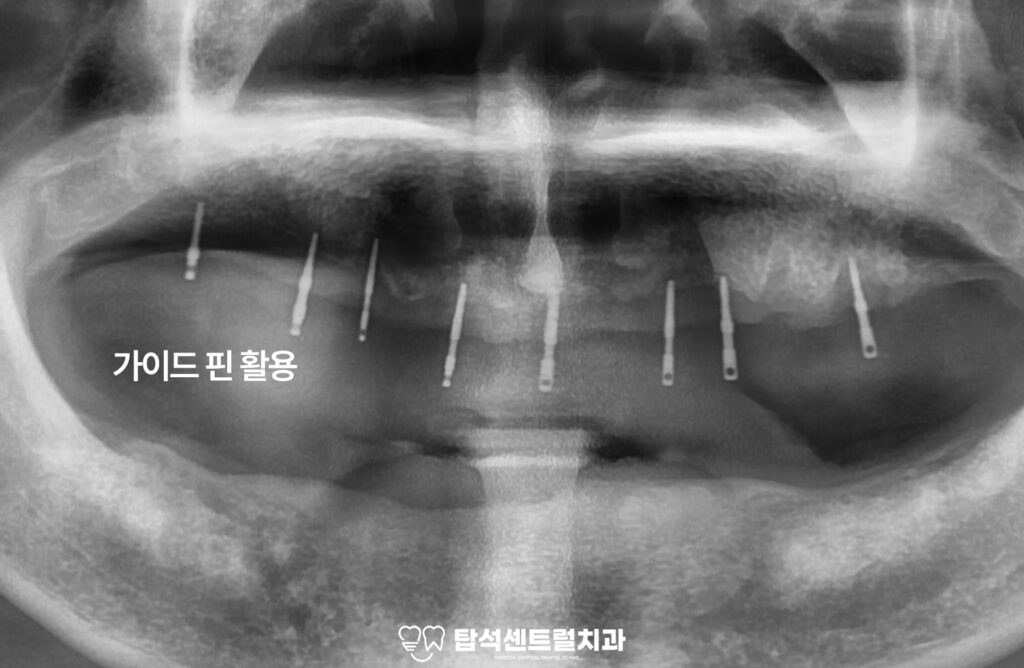

이때 IBS magic guide pin을 활용하면

임플란트의 식립 위치를 정확히 할 수 있으며.

이를 기반으로 수술이 이루어지기 때문에

보다 안전하고 안정적인 결과를

기대해 볼 수 있습니다.

가이드핀을 이용해 임플란트 식립 위치를

정확히 확인할 수 있기 때문에

상악과 마찬가지로 하악 또한

가이드핀을 활용하여

정확한 위치와 각도를 확인합니다.